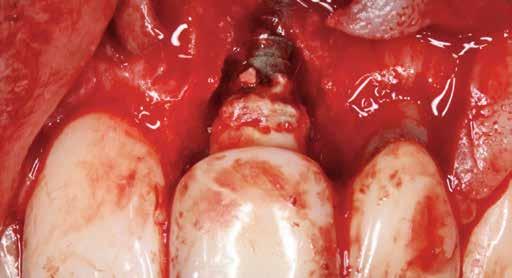

8. ábra: A csonton belüli defektus palatinális nézete. Vegyük észre, hogy a szájpadlás felőli csontfal ép, így ez a defektus alkalmas a regenerációra!

9. ábra: Felvétel az implantátumról és a csontdefektusról a lebenyképzés után, az implantátum és a korona felszínén lévő felesleges rögzítőcement eltávolítása előtt.

10. ábra: A gyulladásos granulációs szövet eltávolítása és az implantátum felületének dekontaminálása után a defektus csonton belüli részét Geistlich Bio-Oss® granulátummal töltjük fel. Megjegyzendő, hogy a korona kontúrja és marginális illeszkedése nem ideális, azonban a páciens nem kívánta a korona eltávolítását.